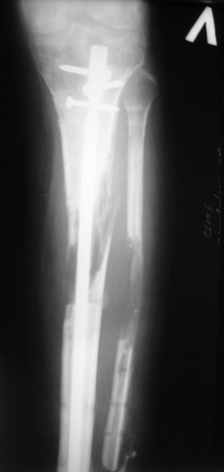

Ситуация пока на следующем этапе:

Больному выполнена резекция малоберцовой кости, ВХО раны, сближение отломков. Резекция м\б через отдельный разрез. После ВХО компрессия в аппарате, края раны сближены наводящими швами (без натяжения).

В случае гладкого заживления раны, при условии положительного решения вопроса с металлом, планируем перемонтаж аппарата Илизарова, дополнительную резекцию дистального отломка, выведение полокости голеностопного сустава в правильное положение (см. боковую Р-грамму), одномоментно остеотомия большеберцовой кости. После восстановления длинны голени, по всей видимости, артродез голеностопного сустава.

Рентгенограммы прилагаются. Фото местного статуса выложу в ближайшее время.

Уважаемые коллеги! В принципе у Вас есть еще время решить дальнейшую тактику, но у меня вопрос: почему остеотомия малоберцовой кости произведена на уровне перелома б/б кости?

Мне кажется надо было произвести косую остетомию в В/з м/б кости!

Так как в данном случае зона вилки ГСС ослаблена (нестабильна), а она вам нужна будет при артродезирования и еще дистальный отломок м/б кости не фиксирована спицей? при билокальном остеосинтезе особенно во время дистракции будут проблемы в данной зоне!

Мы обычно не фиксируем малоберцовую кость. Просто стараемся сопоставить ее концы за счет хорошей репозиции. В представленном случае имеется некоторое смещение дистальных фрагментов кнаружи, и, как мне кажется, ротация их вместе со стопой кнутри (ротация хорошо заметна на прямом снимке по форме таранной кости и на боковом по соотношению отломков малоберцовой). Если это действительно так, то это несложно сейчас постепенно устранить в аппарате. И тогда концы малоберцовой кости будут находиться поближе друг к другу.